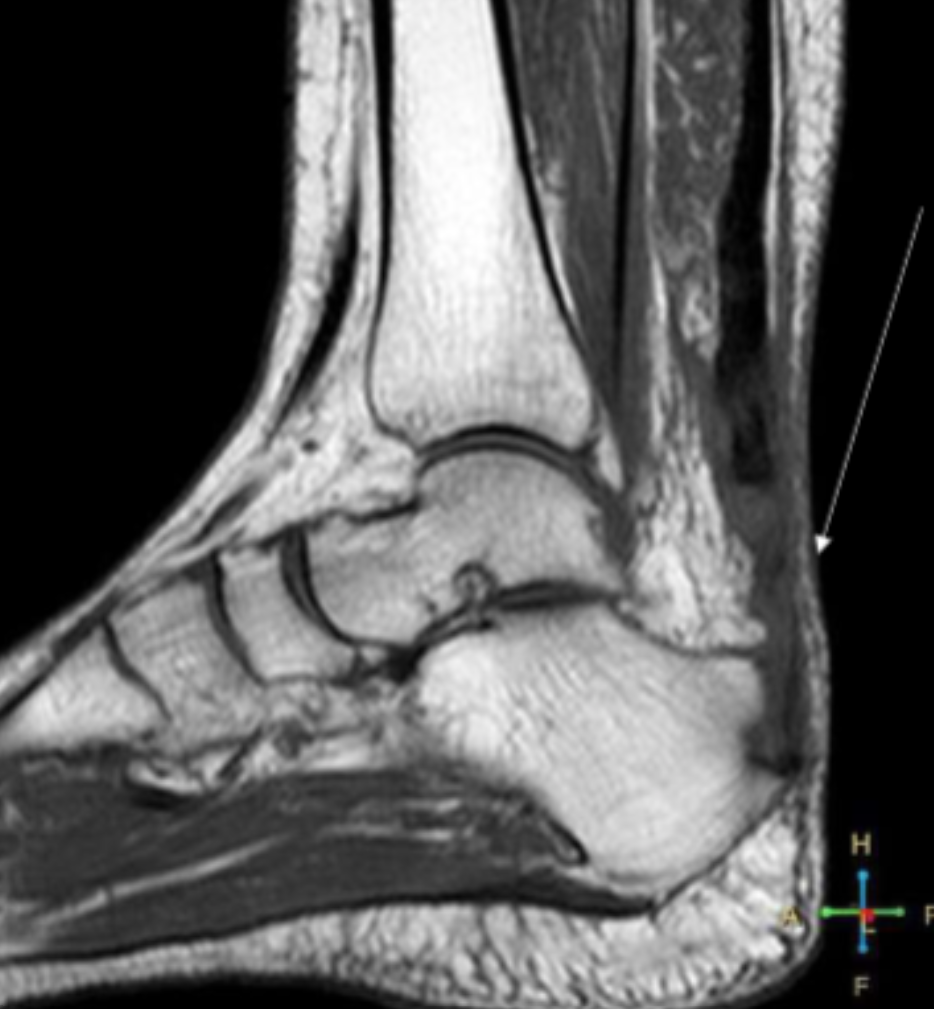

Describe the pathology indicated by the arrow (Sag PD).

Achilles rupture